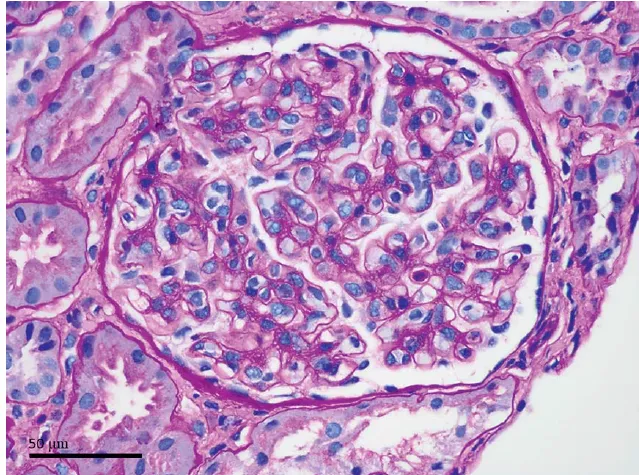

A NCR é uma forma grave e frequentemente irreversível de lesão renal isquêmica, resultante de uma redução prolongada da perfusão arterial renal. Esta condição é geralmente associada à CIVD e apresenta-se com início abrupto de oligúria ou anúria, algumas vezes acompanhada de hematúria macroscópica e dor no flanco. A TC com contraste mostrou a preservação da medula renal e a hipocaptação cortical (rim reverso), confirmando o diagnóstico de NCR.

4. Aproximadamente 85% do fluxo renal é direcionado para o córtex, sendo uma região de alta demanda energética. Uma queda na tensão de oxigênio durante estados de hipotensão hemorrágica é, portanto, mais grave no tecido cortical em comparação com o tecido medular, tornando o córtex mais suscetível à lesão isquêmica.